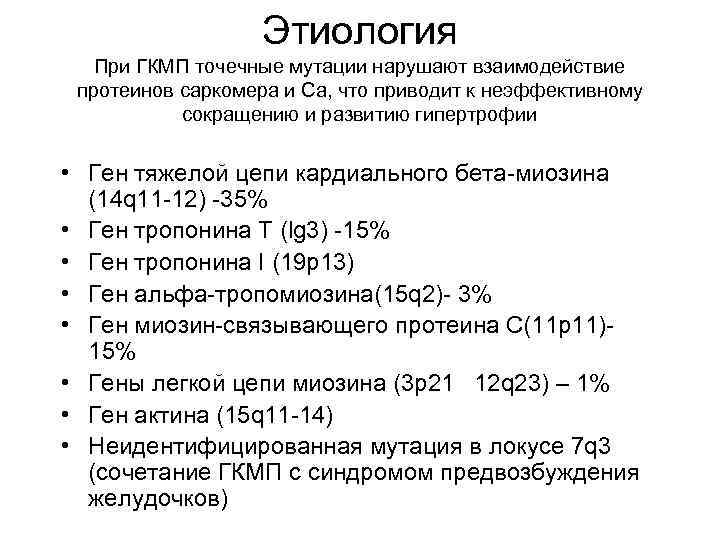

Этиология При ГКМП точечные мутации нарушают взаимодействие протеинов саркомера и Са, что приводит к неэффективному сокращению и развитию гипертрофии • Ген тяжелой цепи кардиального бета-миозина (14 q 11 -12) -35% • Ген тропонина Т (lg 3) -15% • Ген тропонина I (19 р13) • Ген альфа-тропомиозина(15 q 2)- 3% • Ген миозин-связывающего протеина С(11 p 11)15% • Гены легкой цепи миозина (3 p 21 12 q 23) – 1% • Ген актина (15 q 11 -14) • Неидентифицированная мутация в локусе 7 q 3 (сочетание ГКМП с синдромом предвозбуждения желудочков)

Этиология При ГКМП точечные мутации нарушают взаимодействие протеинов саркомера и Са, что приводит к неэффективному сокращению и развитию гипертрофии • Ген тяжелой цепи кардиального бета-миозина (14 q 11 -12) -35% • Ген тропонина Т (lg 3) -15% • Ген тропонина I (19 р13) • Ген альфа-тропомиозина(15 q 2)- 3% • Ген миозин-связывающего протеина С(11 p 11)15% • Гены легкой цепи миозина (3 p 21 12 q 23) – 1% • Ген актина (15 q 11 -14) • Неидентифицированная мутация в локусе 7 q 3 (сочетание ГКМП с синдромом предвозбуждения желудочков)